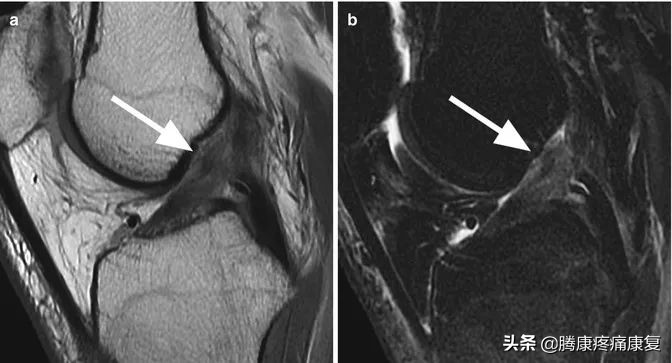

磁共振成像在急性情况下高度敏感。检查可见大量积液、股骨外侧髁和外侧胫骨平台骨挫伤,以及前交叉韧带不显影